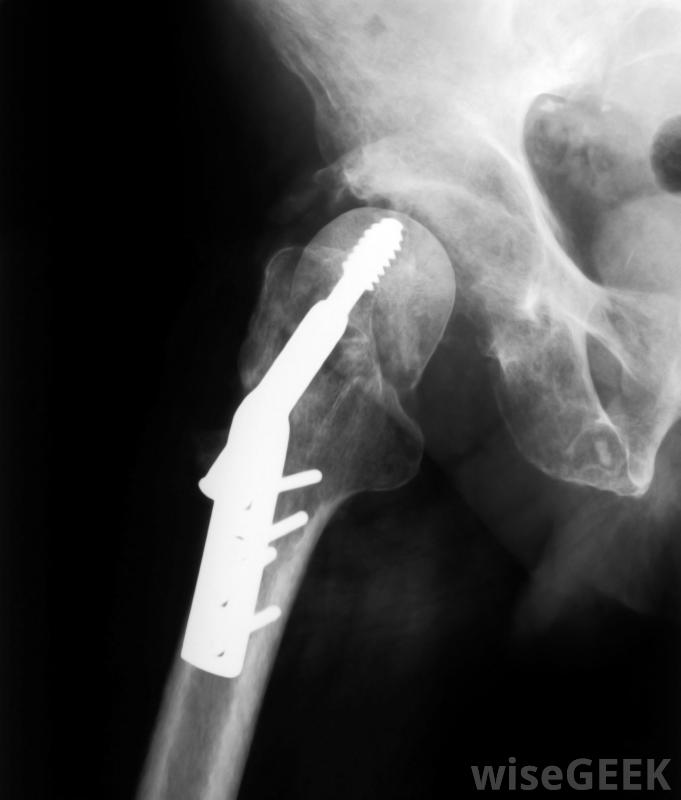

低分子量肝素可用于有高凝血风险的患者,例如低分子量肝素也可用于高危凝血患者的预防性治疗,包括接受髋关节或膝关节置换术的患者和卧床患者,也可使用在某些类型的心脏病发作后和一些心脏手术中,低分子量肝素的工作方式是通过抗Xa因子的作用。血液凝固包括一系列复杂的酶和作用,它们增加抗凝血酶III介导的凝血因子Xa的形成和活性的抑制。在某些情况下,抗Xa会被监测,但这不是常规的。药物是分区域服用的,一天一次或两次,并可在医学专业人士的指导和训练下,自行服用。剂量取决于所开课程的药物,因此会有所不同。任何伴随的药物、疾病、怀孕或哺乳期,在使用前应与医学专业人员讨论,作为相互作用可能发生低分子量肝素会增加出血的风险,使病人更容易受到瘀伤。任何出血迹象,包括瘀伤和红色或黑色的柏油粪便或尿液,应立即报告医生。低分子量肝素通常是短期使用。治疗的持续时间将被确定低分子量肝素是可注射药物。